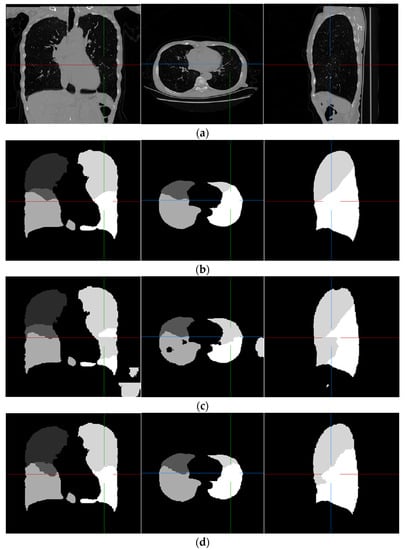

Examples of pulmonary lobe segmentation are shown in Figure 4 and Figure 5 for qualitative visualization. In Figure 4, a case with a general morphology of the lung is presented. In Figure 5, a case with morphological specificity is selected.

Figure 5.

An example of the results of the experiment, which is largely different from the training dataset. (a) Original scan; (b) ground-truth; (c) FRV-Net; and (d) proposed method.

From Figure 4 and Figure 5, it is easy to observe that the results of the FRV-Net are interfered with by the false identification in the background. Additionally, there are irrational holes in the segmented lobe of the FRV-Net. Figure 4 shows that the proposed method could obtain a comparable segmentation result with the FRV-Net method. While in cases with large anatomical differences in the training dataset, the proposed method could avoid a wide range of misclassifications, owning to the aid of the fissures (see Figure 5).

The dice coefficient of the revised FRV-Net method is significantly improved for the left upper lobe. Even compared with the revised FRV-Net method, the result of the proposed method is competitive. Furthermore, the proposed method could prevent interference from the pathological changes in morphology and avoid unreasonable holes in the segmented lobes. Generally, the proposed method could segment the pulmonary lobes accurately and robustly.

4. Discussion

In view of the low accuracy and instability of lung lobe segmentation in CT data with uneven image quality, this work presented an automatic lobe segmentation method that integrated the information from the fissures, the entire lung, and the prior atlas. The results show that the proposed method is valid for the segmentation of the pulmonary lobes, with an overall dice coefficient of 0.953. Compared with the FRV-Net, the proposed method outperforms it in robustness (refer to Figure 5). A shortcoming of the comparison is that test cases are limited due to the lack of manually lobe-labeled data. In further research, the effectiveness of the proposed method is expected to be verified by another annotated dataset.